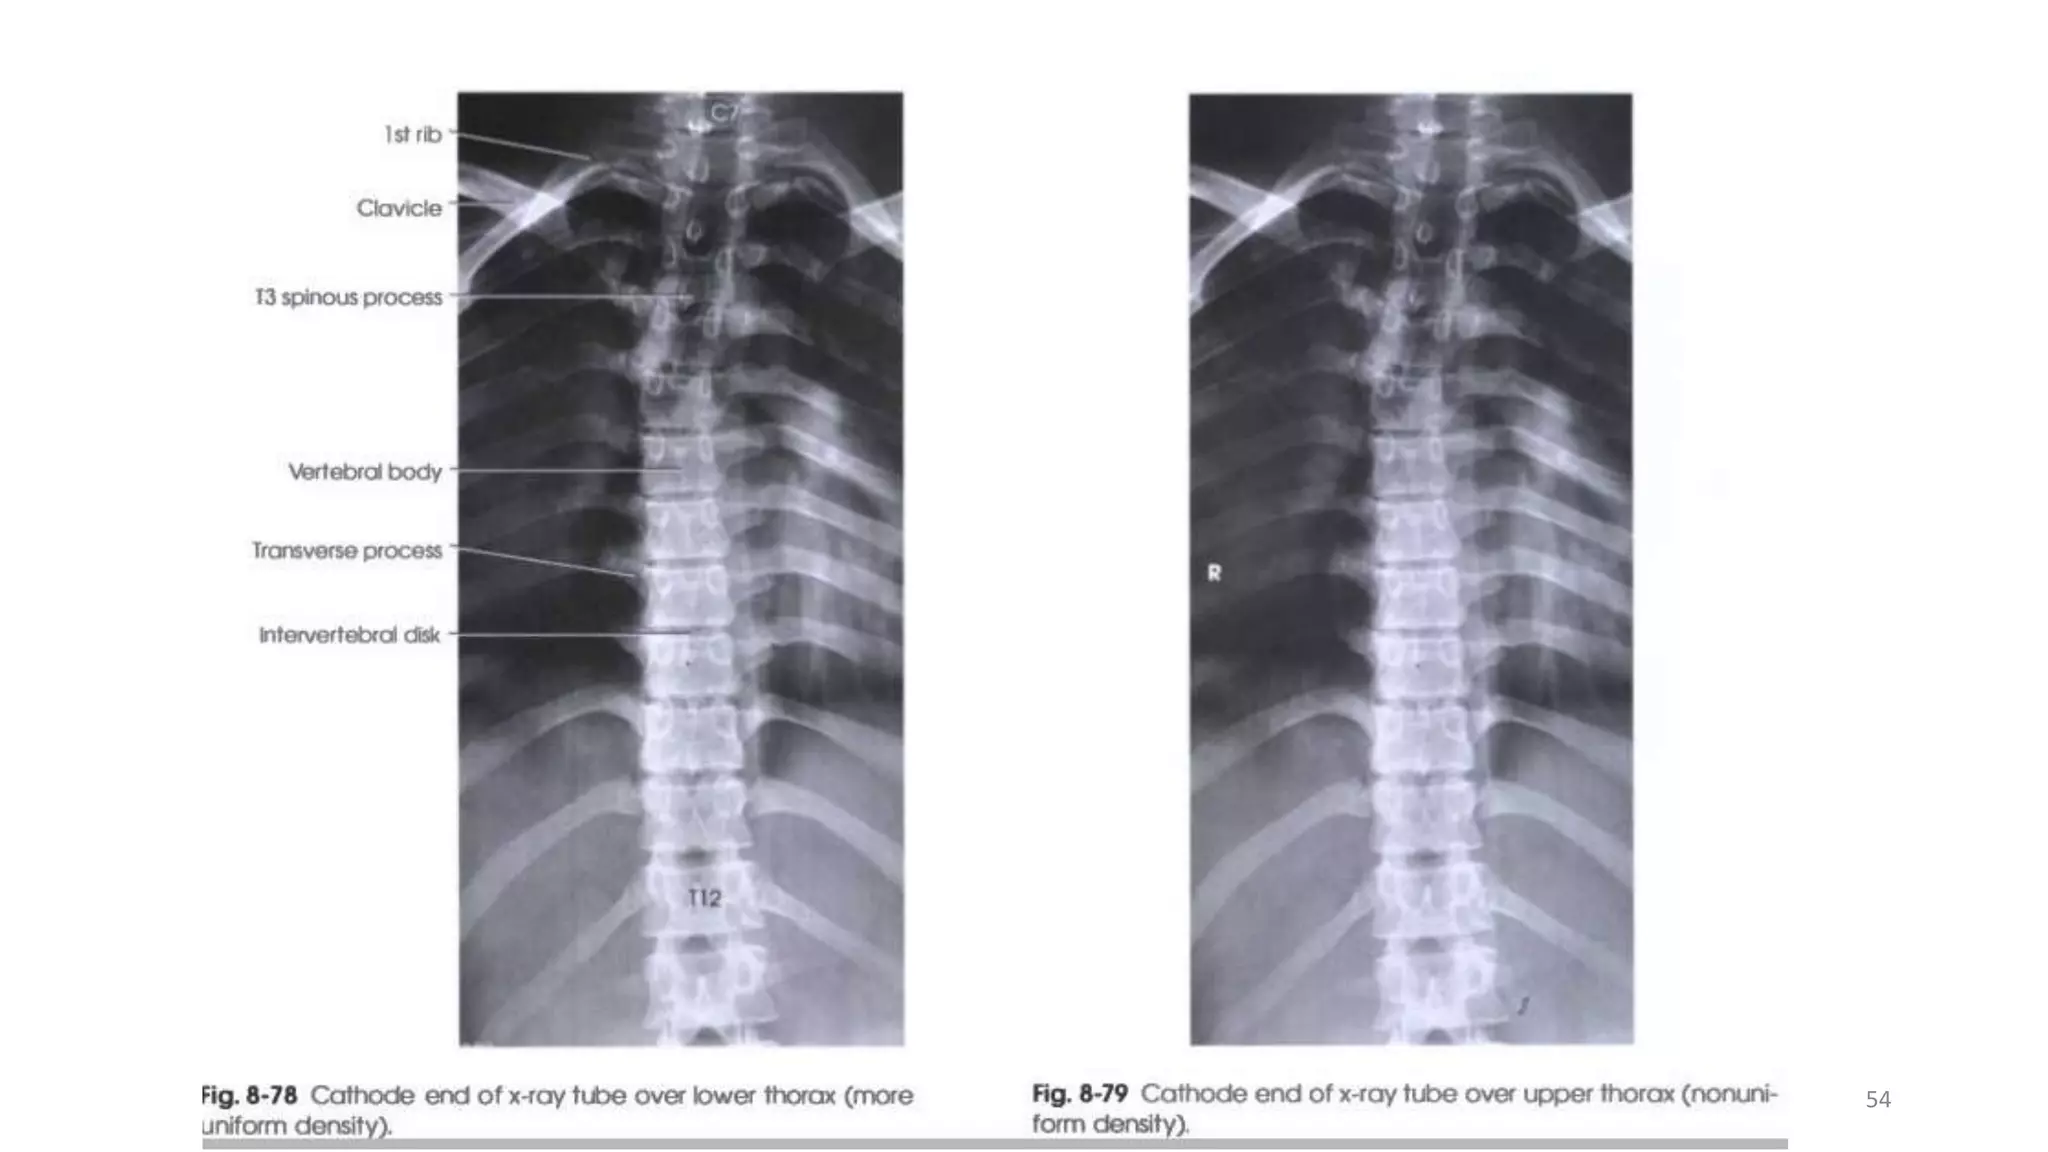

Ap view supine

• Patient is supine, in the middle of the table

• A low pillow under the knee and ankle joint

for the patient comfort

• Cassette is placed under the table in Bucky

• Make exposure on arrested inspiration. This

will cause the diaphragm to move down

over the upper lumbar vertebra, thus

reducing the chance of a large density

difference appearing on the image from

superimposition of the lungs.

CENTERING RAY

• Centered in the midline mid-way

between the cricoid cartilage &the

xiphoid process of the sternum,

approximately 2.5cm below the sternum

angle. (T7)

ESSIANTAL IMAGE CRITERIA

• The image should be include the vertebra

from (C7-L1)

• The image density should be sufficient to

demonstrate bony detail for the upper as

well as the thoracic lower vertebrae.